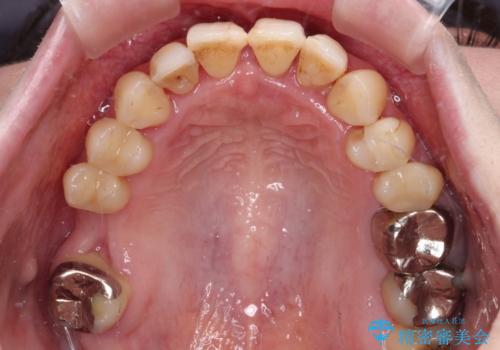

- かかりつけ医にて歯周病治療の名目で治療を行っていたものの、治療プランが明確でないままにインプラント処置を行うとことに疑問を感じ、来院された患者様です。

かかりつけ医では、歯周病治療は終了したため、抜歯を行った右上奥歯にインプラント埋入を行うとの案内があったそうです。

検査を行ったところ、歯周外科処置や抜歯が必要と思われる箇所が散見されたため、あらためて当院に歯周病の初期治療から行うこととしました。

下顎前歯の叢生も気になっており、矯正治療も並行して進めていくこととしました。

自他共に認める、非常に色白の患者様であったため、黄ばんだ歯の色を白くすることを希望されており、歯周病治療の該当部位に限らず、全顎的にオールセラミッククラウンにて補綴治療を行うこととしました。